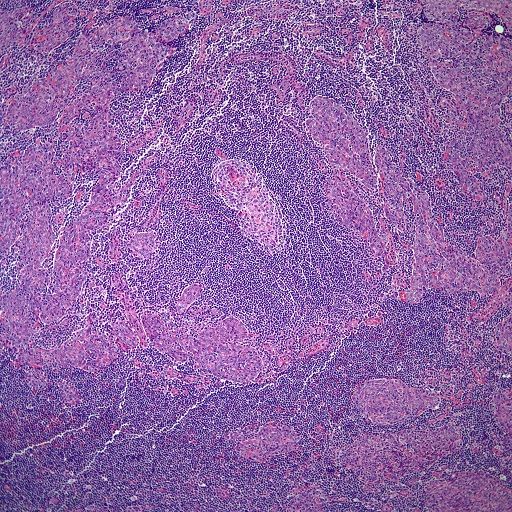

A 48-year-old man presents with dyspnea and cough. Imaging shows an anterior mediastinal mass, and resection of the mass is performed. What is your diagnosis?

Based on the image shown, what is your diagnosis?